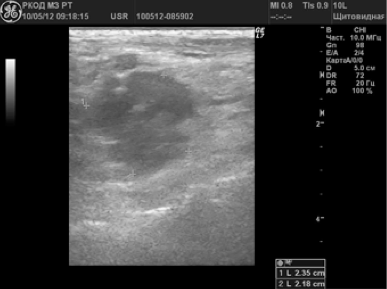

În 58 (38,2%) cazuri a fost suspectat ganglionilor limfatici metastatic. Alterarea LT avea dimensiuni de 6 până la 65 mm; 72,4% din nodulii limfatici au avut o formă sferică, P / PP<2,0; 10,3% — овальную, П/ПЗ>2,0; 17,3% - o formă neregulată sub formă de conglomerate. În 24 (41,4%) pacienți au fost identificați un singur ganglionilor limfatici schimbare; 34 (58,6%) - multiple. In 79,3% din ganglionii limfatici a fost nici o diferențiere în cortexul și poarta; 20,7% - poarta de acces determinat ca un mic incluziuni hiperecogene. 70,8% au fost ganglionii limfatici gipoehogennymi (Figura 3). 12% - anehogennoe; 17,2% - structura neomogena cu porțiuni ridicate și ecogenicitate coborâte clorhidric cu incluziuni lichide și calcifieri (Figura 4.).

Neck metastaze nodul limfatic in cancerul tiroidian

Metastataz structură solidă-lichidă nodul limfatic la nivelul gâtului